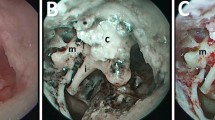

Image analysis and radiomics

Axial HRCT image series from both centers were used for radiomics analysis. For feature extraction, a semi-automatic approach was selected using publicly available software MaZda 4.6 (http://www.eletel.p.lodz.pl/programy/mazda). In all cases, two board-certified radiologists with 6 years of experience each in consensus chose one representative slice and placed a single 2D circular region of interest (> 4 mm2) in the center of the middle ear lesion (Fig. 1). A particular slice was chosen to capture the lesion in its largest extent while at the same time preserving adequate distance from surrounding anatomical structures. Gray-level normalization was applied in every region of interest to reduce potential influences of brightness and contrast variations on feature quantification [11], limiting dynamics to μ ± 3σ (μ, gray-level mean; σ, standard deviation) [12]. A multitude of radiomic features (n = 279 per lesion) from the following categories of radiomic features were extracted from the manually defined regions of interest: first-order histogram (HIS; n = 9; gray-level statistics such as percentiles), co-occurrence matrix (COM; n = 220; distribution of pixel pairs with predefined gray-level values and interpixel distances), run-length matrix (RUN; n = 20; distribution of runs of pixels with the same gray-level value), absolute gradient (GRA; n = 5; degree/abruptness of gray-level value changes between neighboring pixels), autoregressive model (ARM; n = 5; degree of gray-level randomness/regularity), and discrete Haar wavelet transform (WAV; n = 73; frequency content of an image at different scales). The full list of radiomic features that MaZda is capable of calculating can be found at http://www.eletel.p.lodz.pl/programy/mazda/download/FeaturerList.pdf.

Left: unenhanced high-resolution computed tomography (HRCT) image of a 54-year-old female patient with middle ear inflammation (MEI) in the right tympanic cavity (a). Right: unenhanced HRCT image of a 19-year-old male patient with a cholesteatoma in the left tympanic cavity (b). Both show soft tissue in the middle ear without bone destruction. Radiomics characteristics derived from unenhanced HRCT-differentiated MEI from cholesteatoma with an overall median area under the receiver operating characteristic curve (AUC) of 0.78 (separate accuracies: center A, 66%; center B, 84%) in our patient collective. Post-processing in terms of data resampling and harmonization yielded overall median AUCs of 0.88, and 0.89, respectively